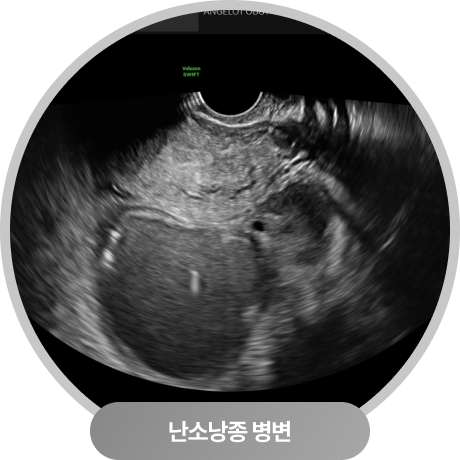

난소낭종 알콜경화술 치료 효과

황체낭종, 자궁내막종

치료 결과

이 케이스 경우 한쪽 난소에서 황체낭종과 자궁내막종이 동시에 발견되어,

두 병변을 모두 알콜경화술로 안전하게 흡입·치료하였습니다.

이처럼 초음파 유도하에 병변을 정확히 확인하고 내용물을 제거한 뒤, 에탄올을 주입하여

재발 가능성을 줄이는 방식으로 난소를 최대한 보존하면서 치료가 가능합니다.